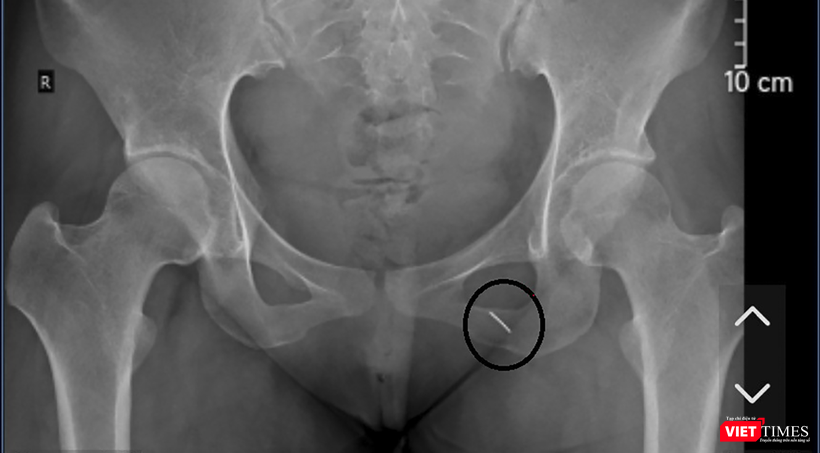

Phim X-quang thể hiện cây kim may đâm và chui sâu vào cơ thể bệnh nhân

Khai thác tiền sử bệnh án, người bệnh nghi ngờ ngồi vào chiếc kim khâu may vá dài 5cm. Tuy nhiên, do người phụ nữ đang mang thai nên không thể tiếp xúc với tia X, buộc các bác sĩ phải chỉ định chụp X-quang để định vị dị vật bằng cách mặc áo chì.

BSCKII Kiều Quốc Hiền cho biết các bác sĩ đã sử dụng hệ thống máy siêu âm 3D thường được sử dụng trong định vị sỏi khi tán sỏi qua da trang bị tại phòng mổ, nên đã định vị được dị vật và phẫu thuật thành công, lấy được cây kim khâu dài 5cm, nằm sâu trong cơ mông của người bệnh.